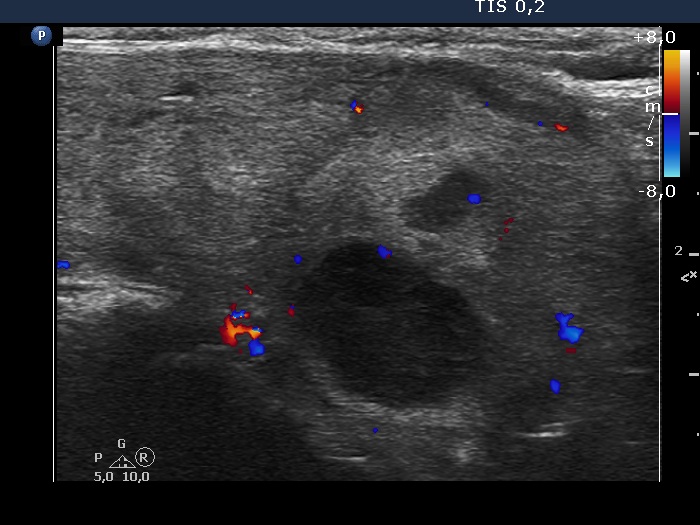

Lower part of the left lobe, longitudinal scan, color Doppler mode. The vascularization is not specific.